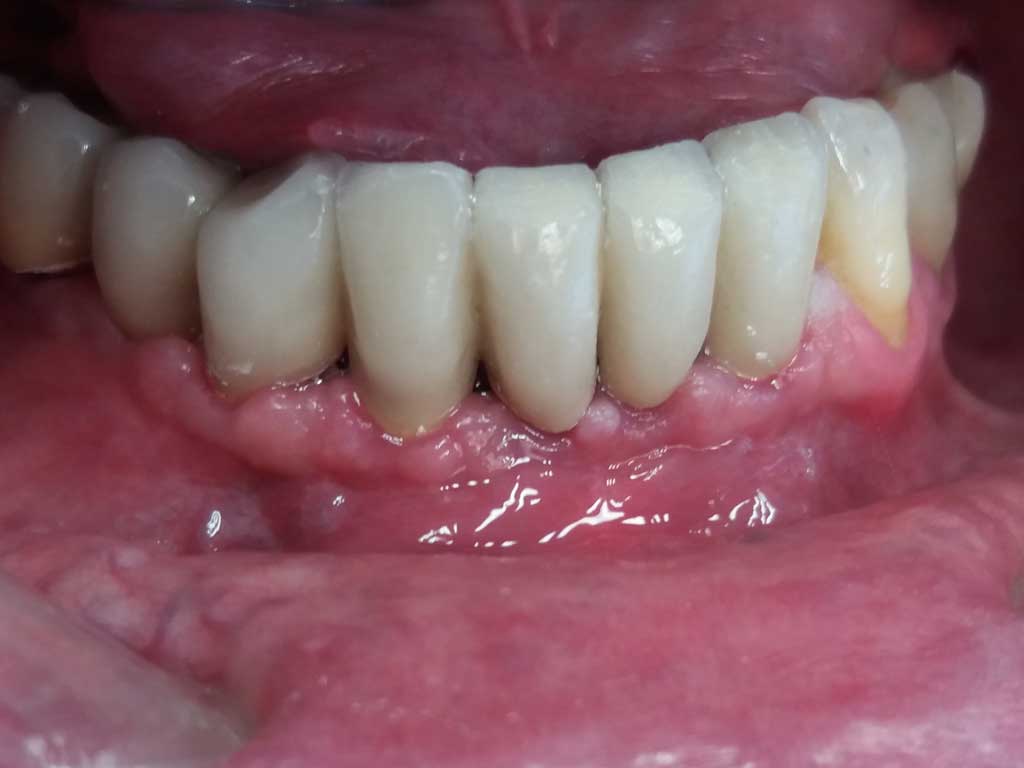

A gengiva completamente guarita , dopo 3 mesi circa dall'inserimento degli impianti, è stato consegnato il lavoro definitivo.

DOPO